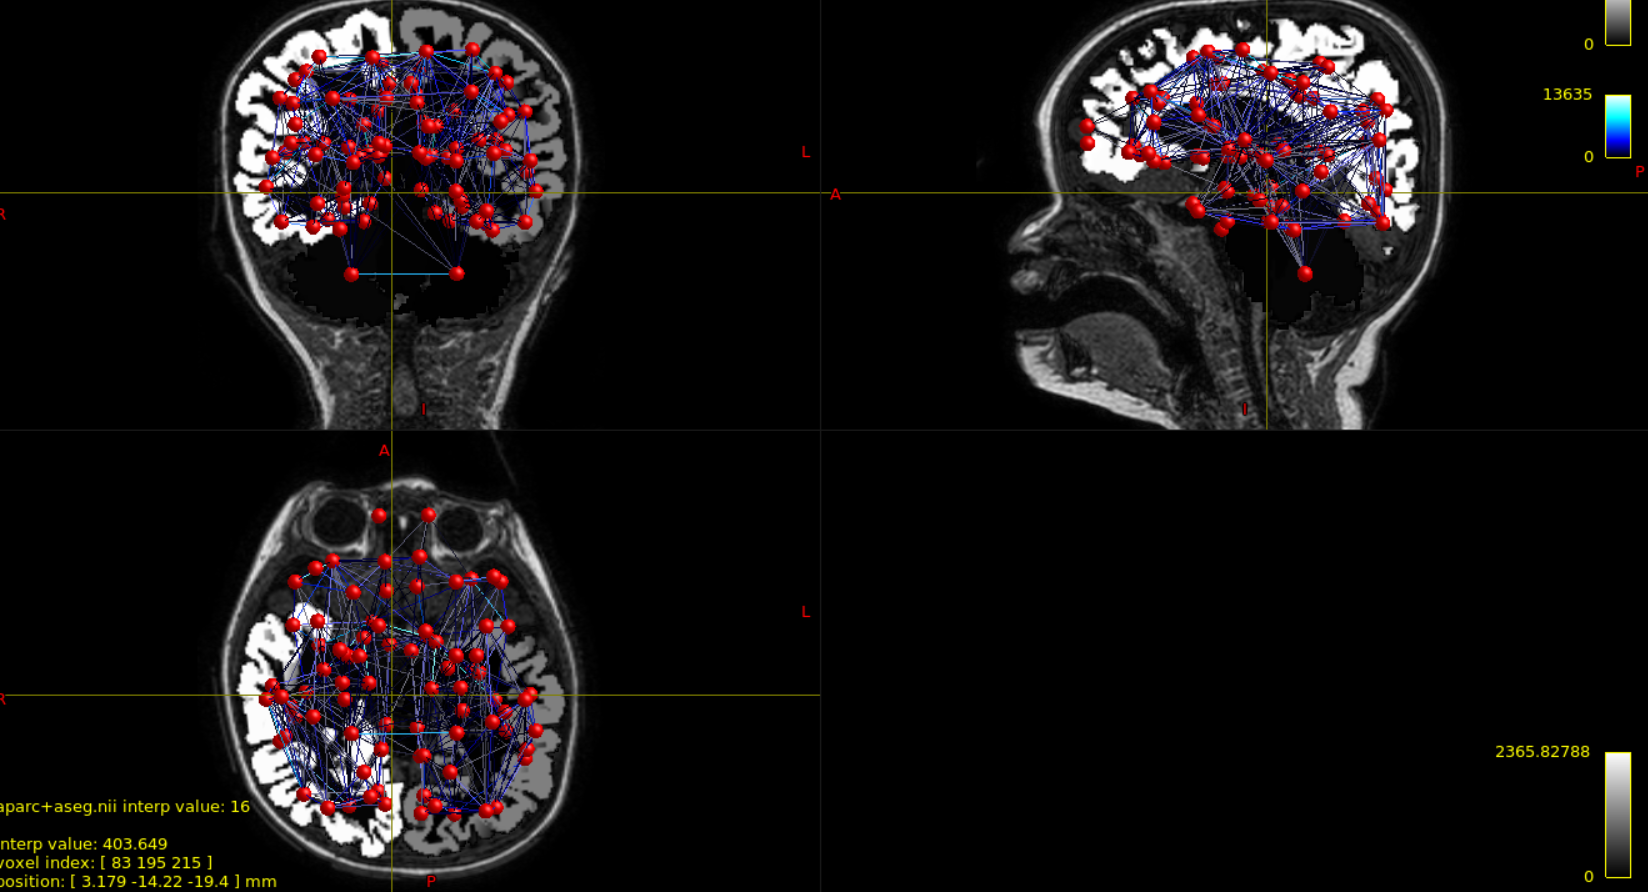

I simply wanted to make sure what I do (both for individual subjects and for consensus) is correct. The resulting connectome I obtain for one example subject is attached in the figures, and I can observe that:

1) nodes do not seem to be perfectly overlaid on the surface (maybe that is just because cerebellum is included in the parcellation, thus causing some nodes to appear outside the pial surface)

2) connections between nodes are "strangely" distributed (i.e., not symmetrical).

In the figures, I selected all nodes and edges with no exclusion/thresholding criteria.

this is just to update you that I have tried visualizing the same example subject with Mrtrix3, and it seems input data are correct. As you can observe from the attached picture, aparc+aseg image excludes cerebellum and thus some nodes are outside it. The surface I use with BNV is created from this segmentation, so I think the outcome I obtain is expected.